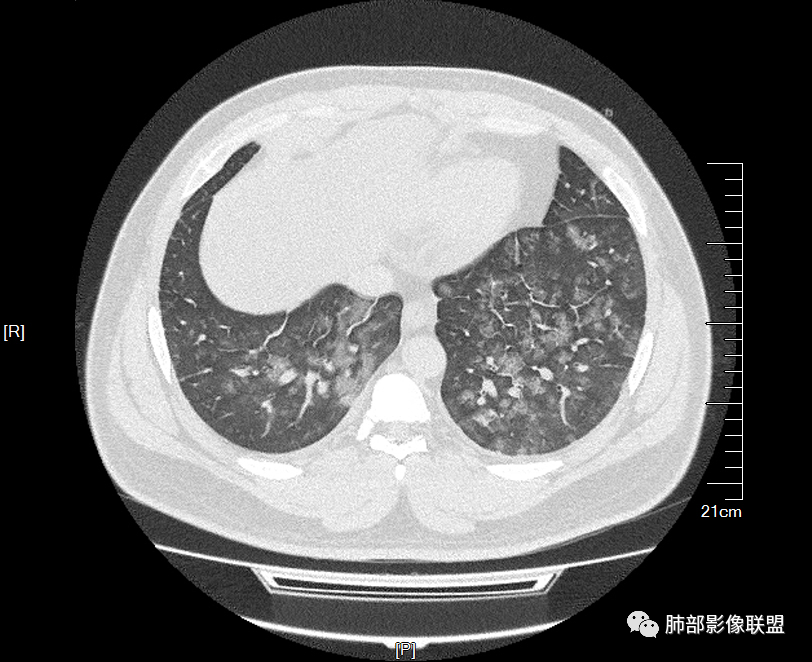

双肺多发弥漫性磨玻璃结节影,大小不一,形态不规则,部分融合,支气管未见明显扩张,部分血管束略增粗,叶裂胸膜增厚,临床有痛风,左足痛6天,考虑:1:痛风结节(一般实性结节,很少磨玻璃结节影)2:血管炎?3:病毒性肺炎(水痘-疱疹肺炎?)

双肺多发腺泡结节及磨玻璃,小叶间隔增厚(大网格状),腺泡结节内及磨玻璃内可见细网格影(小叶内间隔增厚),影像表现符合肺泡出血改变,血肌酐升高,考虑肺肾综合征。鉴别肺水肿。

年轻男性,既往血肌酐升高,左足痛六天入院,有痛风及高血压病史。CT示双肺多发磨玻璃结节影,不规则,部分融合成团或片状,小叶间隔增厚,以双下肺为明显,叶间胸膜亦见增厚。考虑为1.Good-Pasture综合征。2.病毒性肺炎?3.肺水肿?

年轻男性,痛风史,高血压史,肌酐高,左足痛6天入院。胸CT:双肺多发弥漫性磨玻璃结节影,大小不一,部分融合,上中下肺都有,中内带多,胸膜下少。部分血管束略增粗,小叶内间隔、小叶间隔增厚,下肺明显,左室大。叶裂胸膜增厚。临床有痛风,左足痛6天,考虑:心衰、间质性肺水肿?弥漫性肺泡出血?鉴别:MPA,肺肾综合征,痛风结节等。

青年男性,有肾功能不全史和痛风史,这个影像分布有个典型的特点,全部是以中央间质周围的渗出性改变,这个改变主要就是两种可能,一种是肾功能不全导致的血管通透性增高导致的肾性肺水肿,一种是出血导致的DAH改变,具体是哪种,影像上不好简单的鉴别,需要结合更多临床资料综合分析。

年轻男性,痛风,肌酐高,提示肾功能有损,两肺多发磨玻璃腺泡结节,小叶间隔增厚,双侧少许胸水,血管增粗,考虑肾性肺水肿,DAD,鉴别肺肾综合征,需要更多临床资料

32岁男性,左足痛入院。有痛风、肌酐升高、高血压病史。CT:两肺弥漫磨玻璃结节,小叶间隔增厚、小叶内间质增厚,两侧少量胸水。考虑:1.肺水肿;2.过敏性肺炎;3.肿瘤?

青年男性,双肺多发大小不等斑片状磨玻璃密度影,内见细网格影,并可见小叶间隔增厚,双侧胸腔少量积液,患者曾有血肌酐增高,提示曾有肾损害,并有痛风、高血压病史,考虑肺肾综合征,鉴别过敏性肺炎

小叶间隔增厚,无明显重力趋势

少量积液,脂肪肝

这里有一点重力趋势

中轴间质稍增厚

细网格也明显

中轴间质增厚,小叶间隔增厚,小叶内间质增厚,部分重力作用,双侧对称,胸水,按理淋巴道回流受阻有